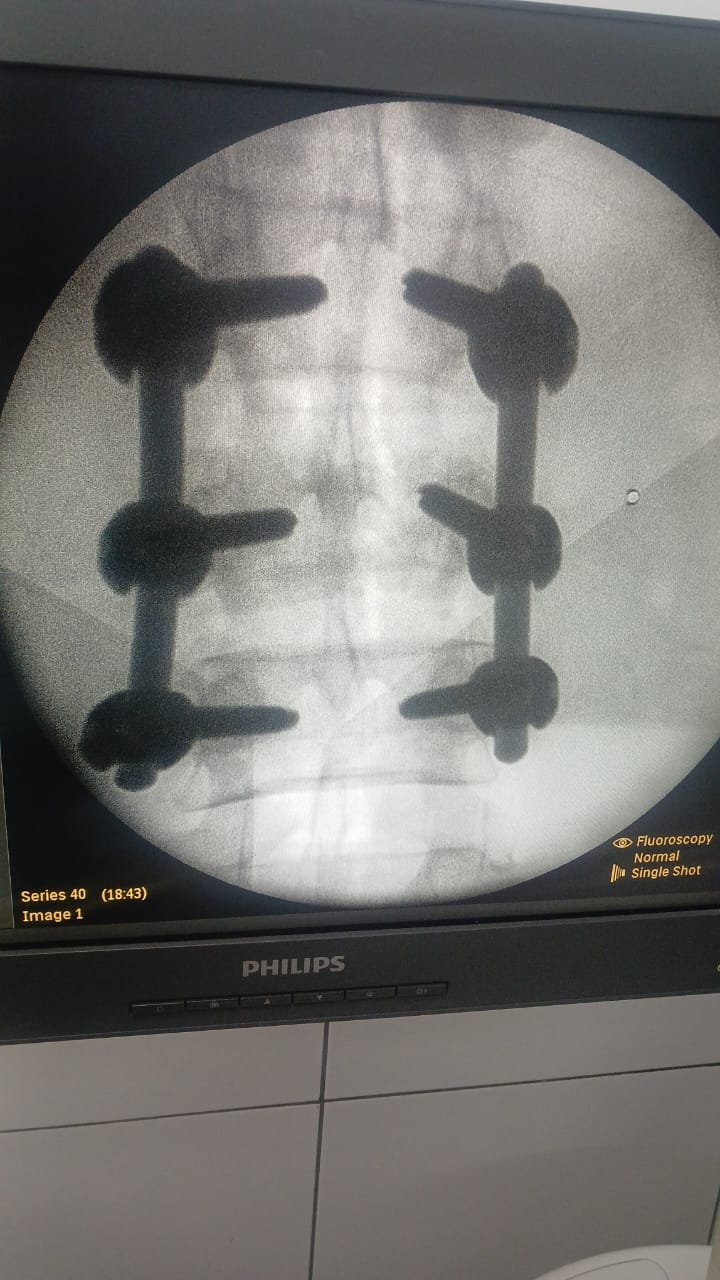

نجح الفريق الطبي بمستشفى ميت غمر المركزي (أ) التابعة لمديرية الصحة بالدقهلية .. في إجراء تدخل جراحي دقيق لمريض كان يعاني من كسر بالفقرة القطنية الثالثة ..

وعلى الفور .. تم تجهيز الحالة ودخولها غرفة العمليات حيث تم إجراء تثبيت للفقرات القطنية مع استعدال للعمود الفقري، مع الحفاظ على كفاءة الأعصاب الطرفية للطرفين السفليين، بما ساهم في استقرار الحالة ومنع حدوث مضاعفات عصبية ..